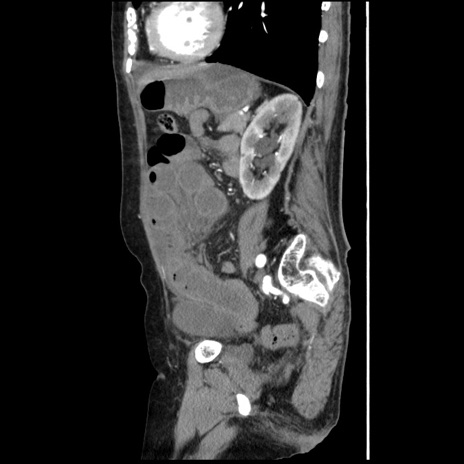

冠状断像